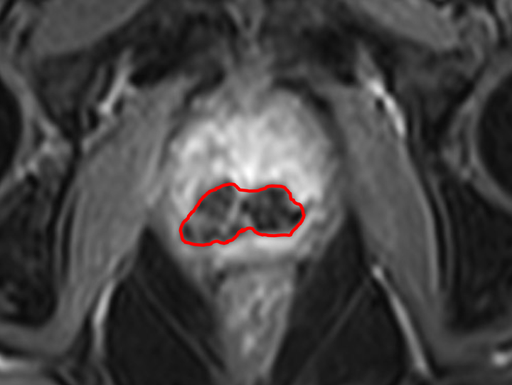

MR-bilder

Bild 2 visar effekten av behandlingen hos patient 10. Behandlingen för patient 10 var fokal, dvs syftet var inte att behandla hela prostatakörteln, utan bara den del där tumören fanns. I bilden visas det som det mörka området i den nedre delen av prostatan. Den ljusa delen av prostatan i övre delen indikerar obehandlad vävnad.